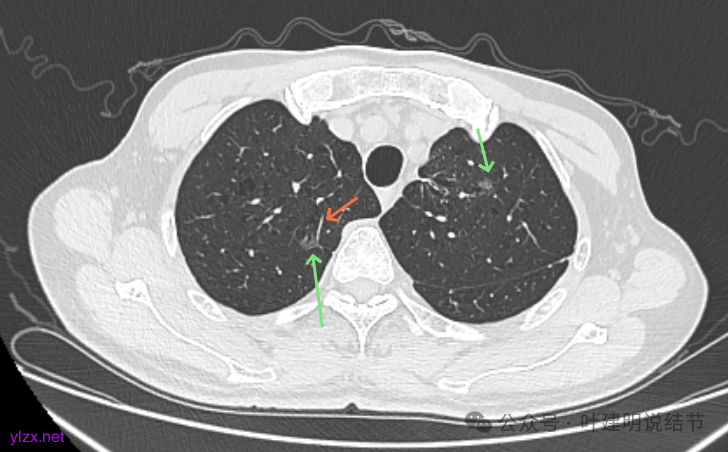

最后看2025年3月的连续层面的影像细节:

右上病灶淡磨密度,有空泡征,整体轮廓较清。

瘤肺边界清楚,空泡征明显。

表面不平,没有实性成分。灶内空泡有些像蜂窝状。

病灶边上有小血管走行,整体轮廓清,没有明显实性成分。

右上病灶淡而纯主要原因,空泡征明显。

左上病灶淡而纯,有微小血管进入。

右上淡磨,轮廓清,空泡明显。

左上的小而局部有细支气管扩张的样子,部分边缘显毛糙,有细毛刺样征。

右上叶病灶有血管贴边,轮廓清;

左上病灶纯磨,轮廓清。

右上淡磨,左下密度较右侧的稍不均一点。